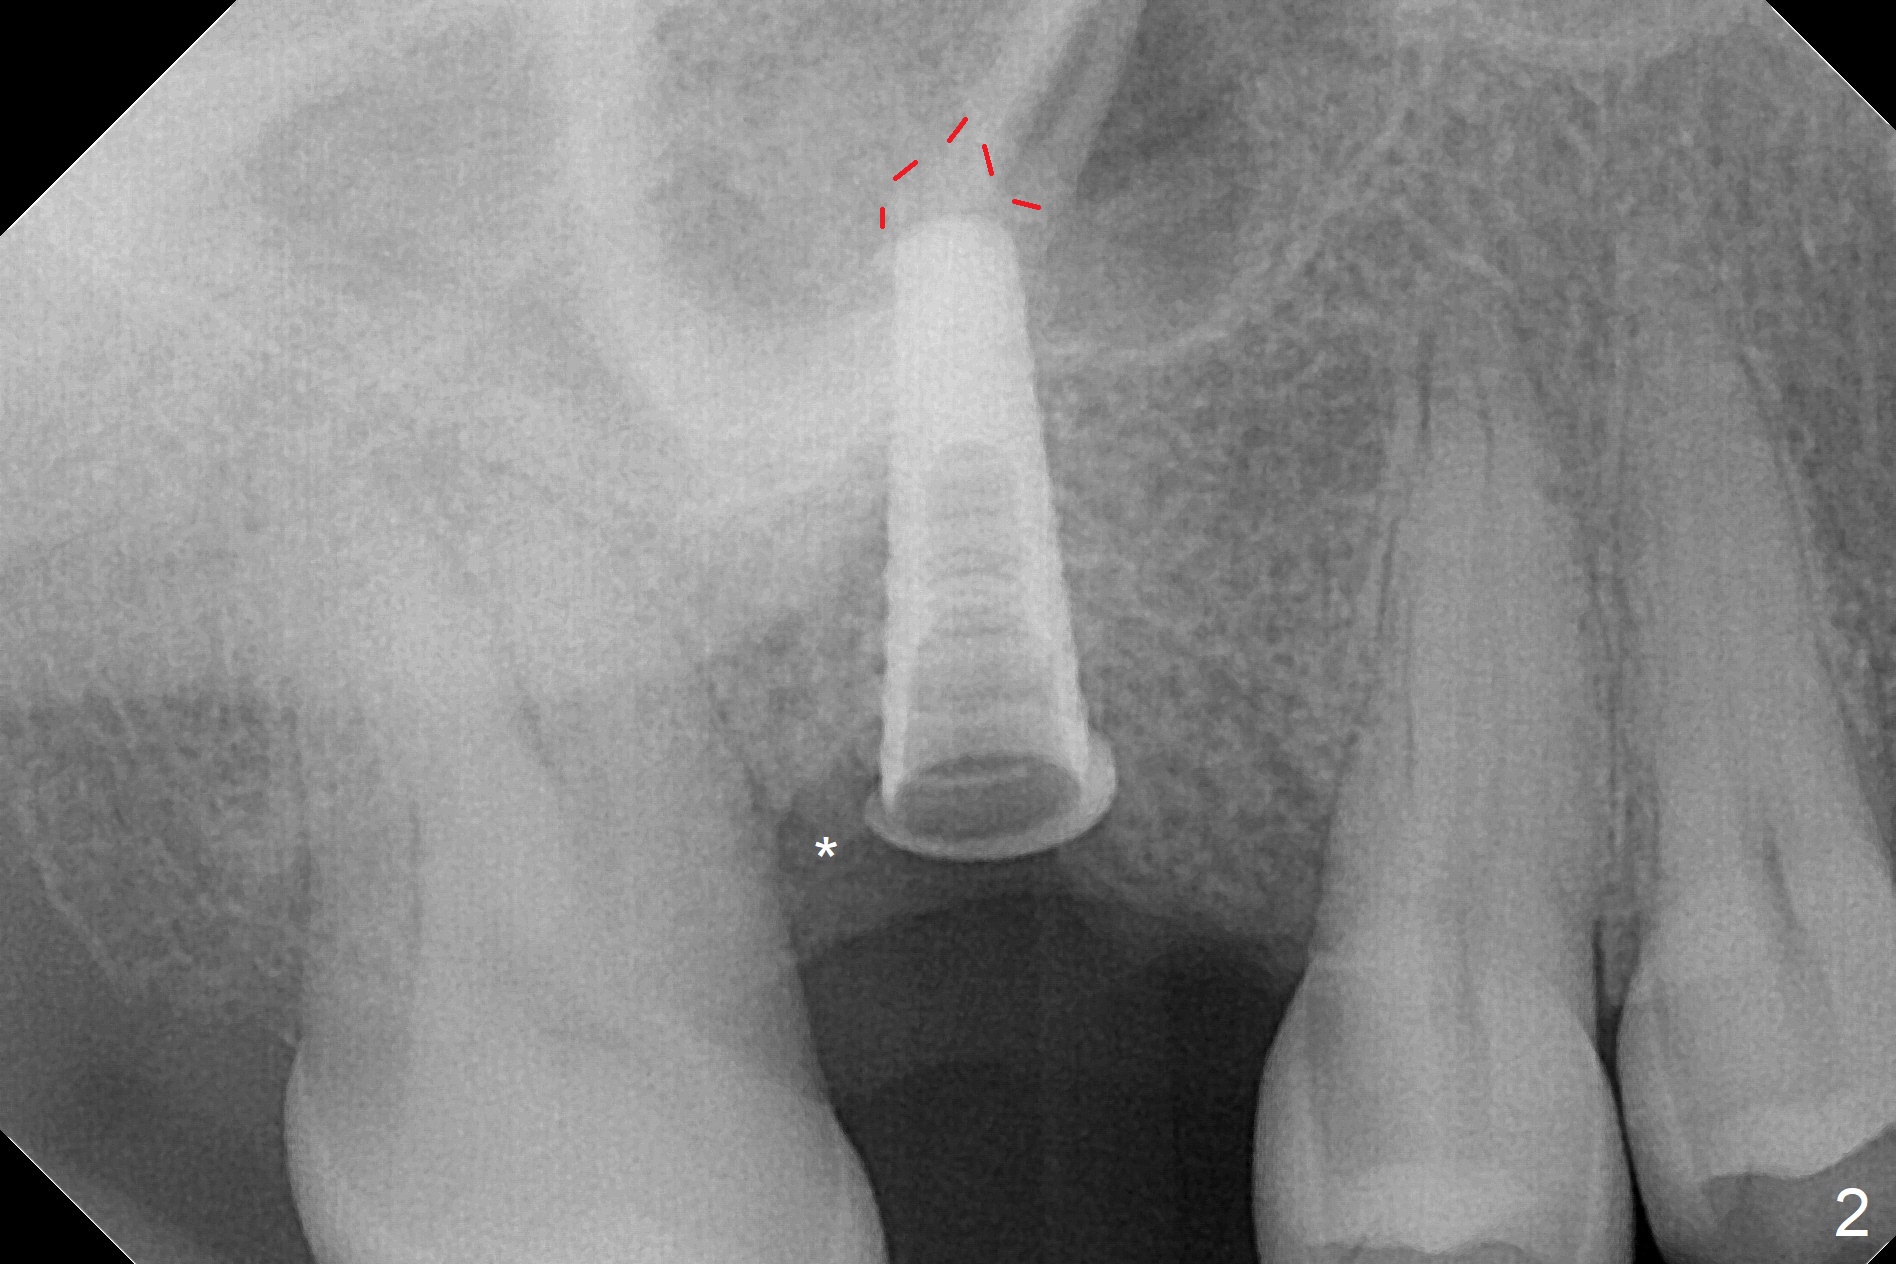

There are 2 sockets at #3 when the residual roots are extracted; osteotomy is established in the palatal one for 11 mm (gingival level; Fig.1), ~ 2 mm from the sinus floor (red dashed line). Following the last drill (3.8 mm) for 11 mm, a 4.5x11 mm dummy implant is placed 2 mm subgingival (Fig.2). In fact the sinus lift (red dashed line) is done by implant insertion, since the bone plug after Magic Drill is present in the apical portion of the osteotomy when the last drill is finished prior to implant placement.. After the dummy implant is removed, the definitive one (the same size) is placed with >50 Ncm, followed by placement of a 4.5x4(3) mm abutment and VeraGraft mixed with autogenous one (Fig.3 *). The most coronal portion of the socket is sealed with collagen plug. The latter is fixed in place by an immediate provisional. The mesial surface of the tooth #2 is reduced (Fig.4 <) prior to provisional fabrication. The implant is placed distal, which could be corrected by pushing the 2nd molar distal orthodontically. There is mild crestal bone loss nearly 8 months postop (Fig.5). An angled abutment (5x15 degrees, 3 mm cuff) is used before impression. CT is taken immediately post cementation (Fig.6 (8.5 months postop)). CT taken 8 months post cementation shows that the 4.5x11 mm implant barely passes the sinus floor (Fig.7). Return to Upper Molar Immediate Implant, Prevent Molar Periimplantitis (Protocols, Table), IBS, 30 19 Xin Wei, DDS, PhD, MS 1st edition 09/13/2017, last revision 01/31/2019